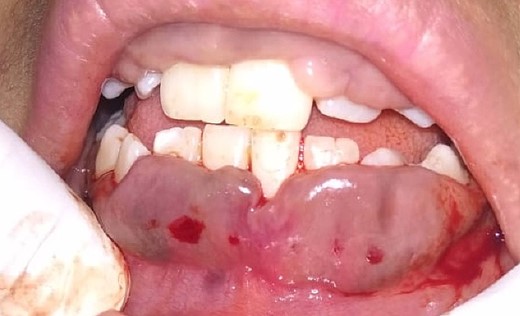

On the day of the procedure, a complete blood test was done which shows normal limit values. Following the administration of local anesthesia, periodontal pockets were checked (Fig. 2) and the bleeding points were marked using a Krane Kaplan pocket marker, (Fig. 3) continuous incision was made with the scalpel and blade no. 15, keeping the bevel at ~45° to the tooth surface. Once the incisions had been made, the excision of the tissue was done with a curette (Fig. 4). Further electrocautery was used as a coagulating machine to control the bleeding. Gingivoplasty, i.e. reshaping and recontouring of gingiva following the normal festooned pattern was done. Coe-Pak was placed and the patient was recalled after 1 week for check-up (Fig. 5).